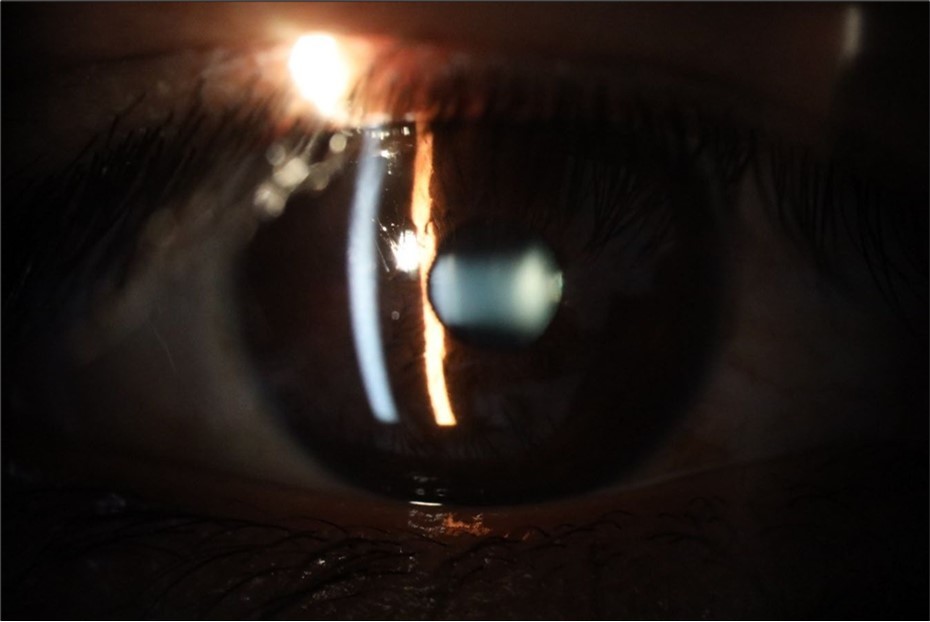

Figure 25.Mirror reflection of the affected eye (right side), with good appearance. This indicates that the transparent media of the eyeball (Cornea, anterior chamber, lens, and vitreous) are in good condition.

Figure 26.The macrograph of the anterior segment of the right eye (affected) shows very good transparency of the cornea, anterior chamber, lens, and vitreous.

Figure 31.The photograph of the right eye shows an almost normal mirror reflection, as well as a better pupillary dilation.

Figure 32.The macro photograph of the right eye shows us a cornea, anterior camera, and crystalline lens in very good condition.